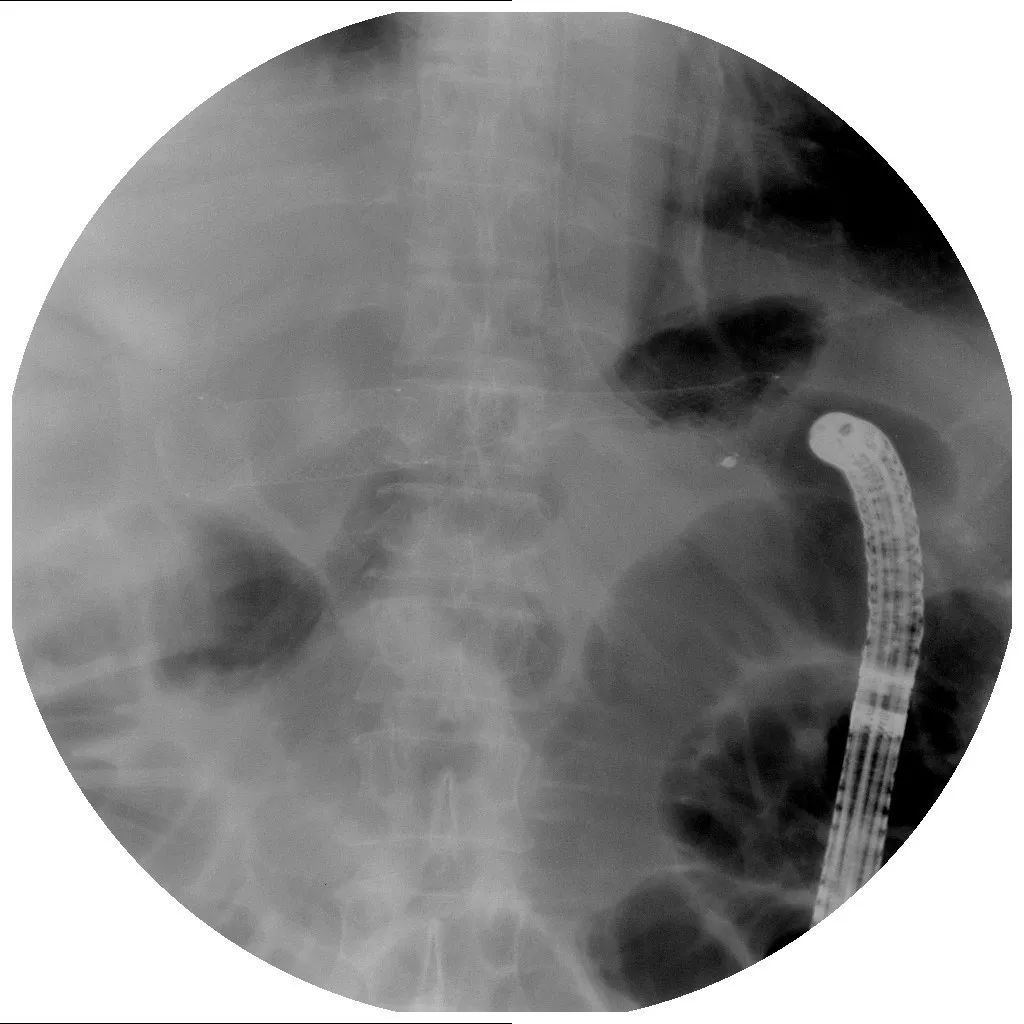

2018年7月初行结肠支架置入术(图4、图5、图6)。

图5 结肠支架置入术

图6 X线腹部平片见结肠支架就位良好,肠梗阻消失

术后呕吐、腹痛、腹胀、发热等症状消失,患者能进半流食,出院回家静养。本以为可以消停一段时间了,但是……